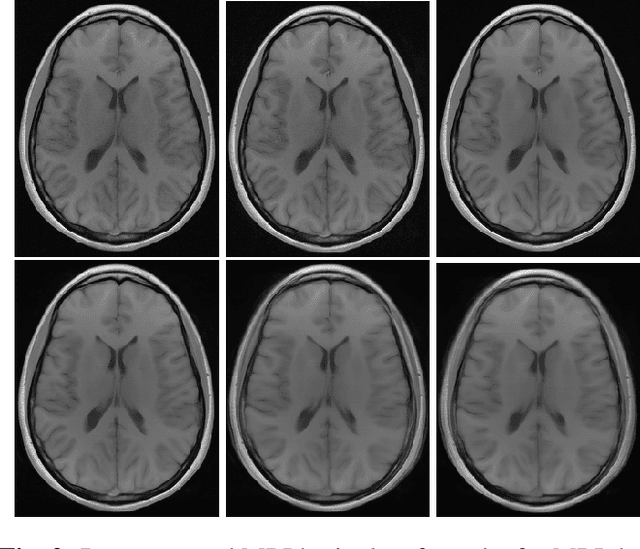

Abstract:Image quality assessment (IQA) is standard practice in the development stage of novel machine learning algorithms that operate on images. The most commonly used IQA measures have been developed and tested for natural images, but not in the medical setting. Reported inconsistencies arising in medical images are not surprising, as they have different properties than natural images. In this study, we test the applicability of common IQA measures for medical image data by comparing their assessment to manually rated chest X-ray (5 experts) and photoacoustic image data (1 expert). Moreover, we include supplementary studies on grayscale natural images and accelerated brain MRI data. The results of all experiments show a similar outcome in line with previous findings for medical imaging: PSNR and SSIM in the default setting are in the lower range of the result list and HaarPSI outperforms the other tested measures in the overall performance. Also among the top performers in our medical experiments are the full reference measures DISTS, FSIM, LPIPS and MS-SSIM. Generally, the results on natural images yield considerably higher correlations, suggesting that the additional employment of tailored IQA measures for medical imaging algorithms is needed.

Abstract:Image quality assessment (IQA) is not just indispensable in clinical practice to ensure high standards, but also in the development stage of novel algorithms that operate on medical images with reference data. This paper provides a structured and comprehensive collection of examples where the two most common full reference (FR) image quality measures prove to be unsuitable for the assessment of novel algorithms using different kinds of medical images, including real-world MRI, CT, OCT, X-Ray, digital pathology and photoacoustic imaging data. In particular, the FR-IQA measures PSNR and SSIM are known and tested for working successfully in many natural imaging tasks, but discrepancies in medical scenarios have been noted in the literature. Inconsistencies arising in medical images are not surprising, as they have very different properties than natural images which have not been targeted nor tested in the development of the mentioned measures, and therefore might imply wrong judgement of novel methods for medical images. Therefore, improvement is urgently needed in particular in this era of AI to increase explainability, reproducibility and generalizability in machine learning for medical imaging and beyond. On top of the pitfalls we will provide ideas for future research as well as suggesting guidelines for the usage of FR-IQA measures applied to medical images.